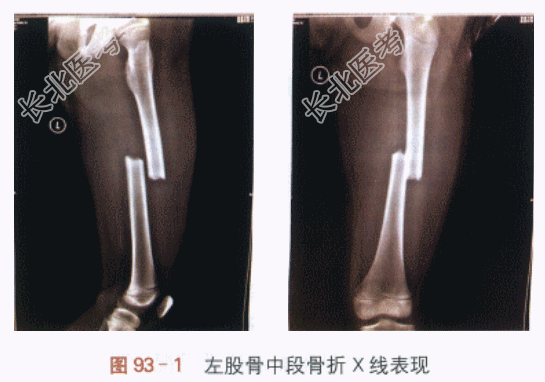

1.现病史患儿,男,5岁,因“被汽车撞伤左大腿,局部畸形肿胀活动受限3h”来诊。患儿入院前3h坐于电瓶车后座不慎被一汽车撞伤左大腿,撞伤后即刻出现左大腿中部畸形肿胀,局部疼痛明显,并伴有左下肢不能活动。患儿被120急送至我院就诊。2.既往史足月顺产第一胎,生后体健,按时接种疫苗,生长发育与同龄儿相同。无手术外伤史。否认家族遗传代谢病史,无传染病接触史。药物无过敏。3.体格检查T36.5℃,HR90次/min,一般情况可,神志清楚,精神反应佳,头面部未见破溃及外伤改变,双瞳孔等大等圆,对光反射灵敏,口鼻腔无出血,口唇无青紫,呼吸平稳;皮肤、巩膜无黄染;无脱水貌;胸廓平坦,三凹征阴性,听诊双肺呼吸音清,未闻及啰音,心音有力,律齐,未闻明显杂音;腹部平软,无压痛,未及包块;右下肢、双上肢活动灵活,颈部活动灵活,脊柱棘突无压痛;肛门生殖器未见畸形。专科查体:由担架抬入诊室,左大腿中段畸形肿胀,局部压痛明显,可及骨擦音,左下肢活动时大腿疼痛明显,活动不能,膝关节无肿胀,无压痛,被动活动可,左足各趾血运活动良好。4.实验室及影像学检查血液学检查未见明显异常。左股骨正侧位片:左股骨中段骨折,骨折端有移位(见图93-1)